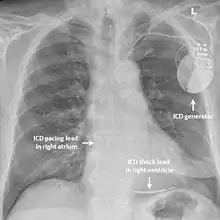

Implantable cardioverter-defibrillator

In those with short QT syndrome who have already experienced a life-threatening abnormal heart rhythm such as ventricular fibrillation, an implantable cardioverter-defibrillator (ICD) may be recommended to reduce the chance of sudden death.[3] This device is implanted under the skin and can continually monitor the heart rhythm. If the device detects a dangerous heart rhythm disturbance it can deliver a small electric shock with the aim of restoring a rhythm. Implanting an ICD in someone with short QT syndrome who has not yet experienced a life-threatening arrhythmia is more controversial but may be considered.[1][11]